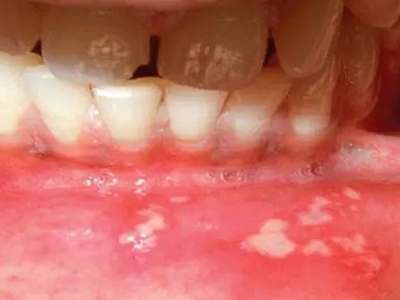

唇内侧

溃疡

溃疡性口炎下嘴唇内侧有白色假膜图

溃疡性口炎患者下嘴唇内侧黏膜上有散在分布的溃疡,周围黏膜红肿,其上附有黄白色假膜,随着病情进展,溃疡会逐渐增多,应及时进行抗感染治疗。